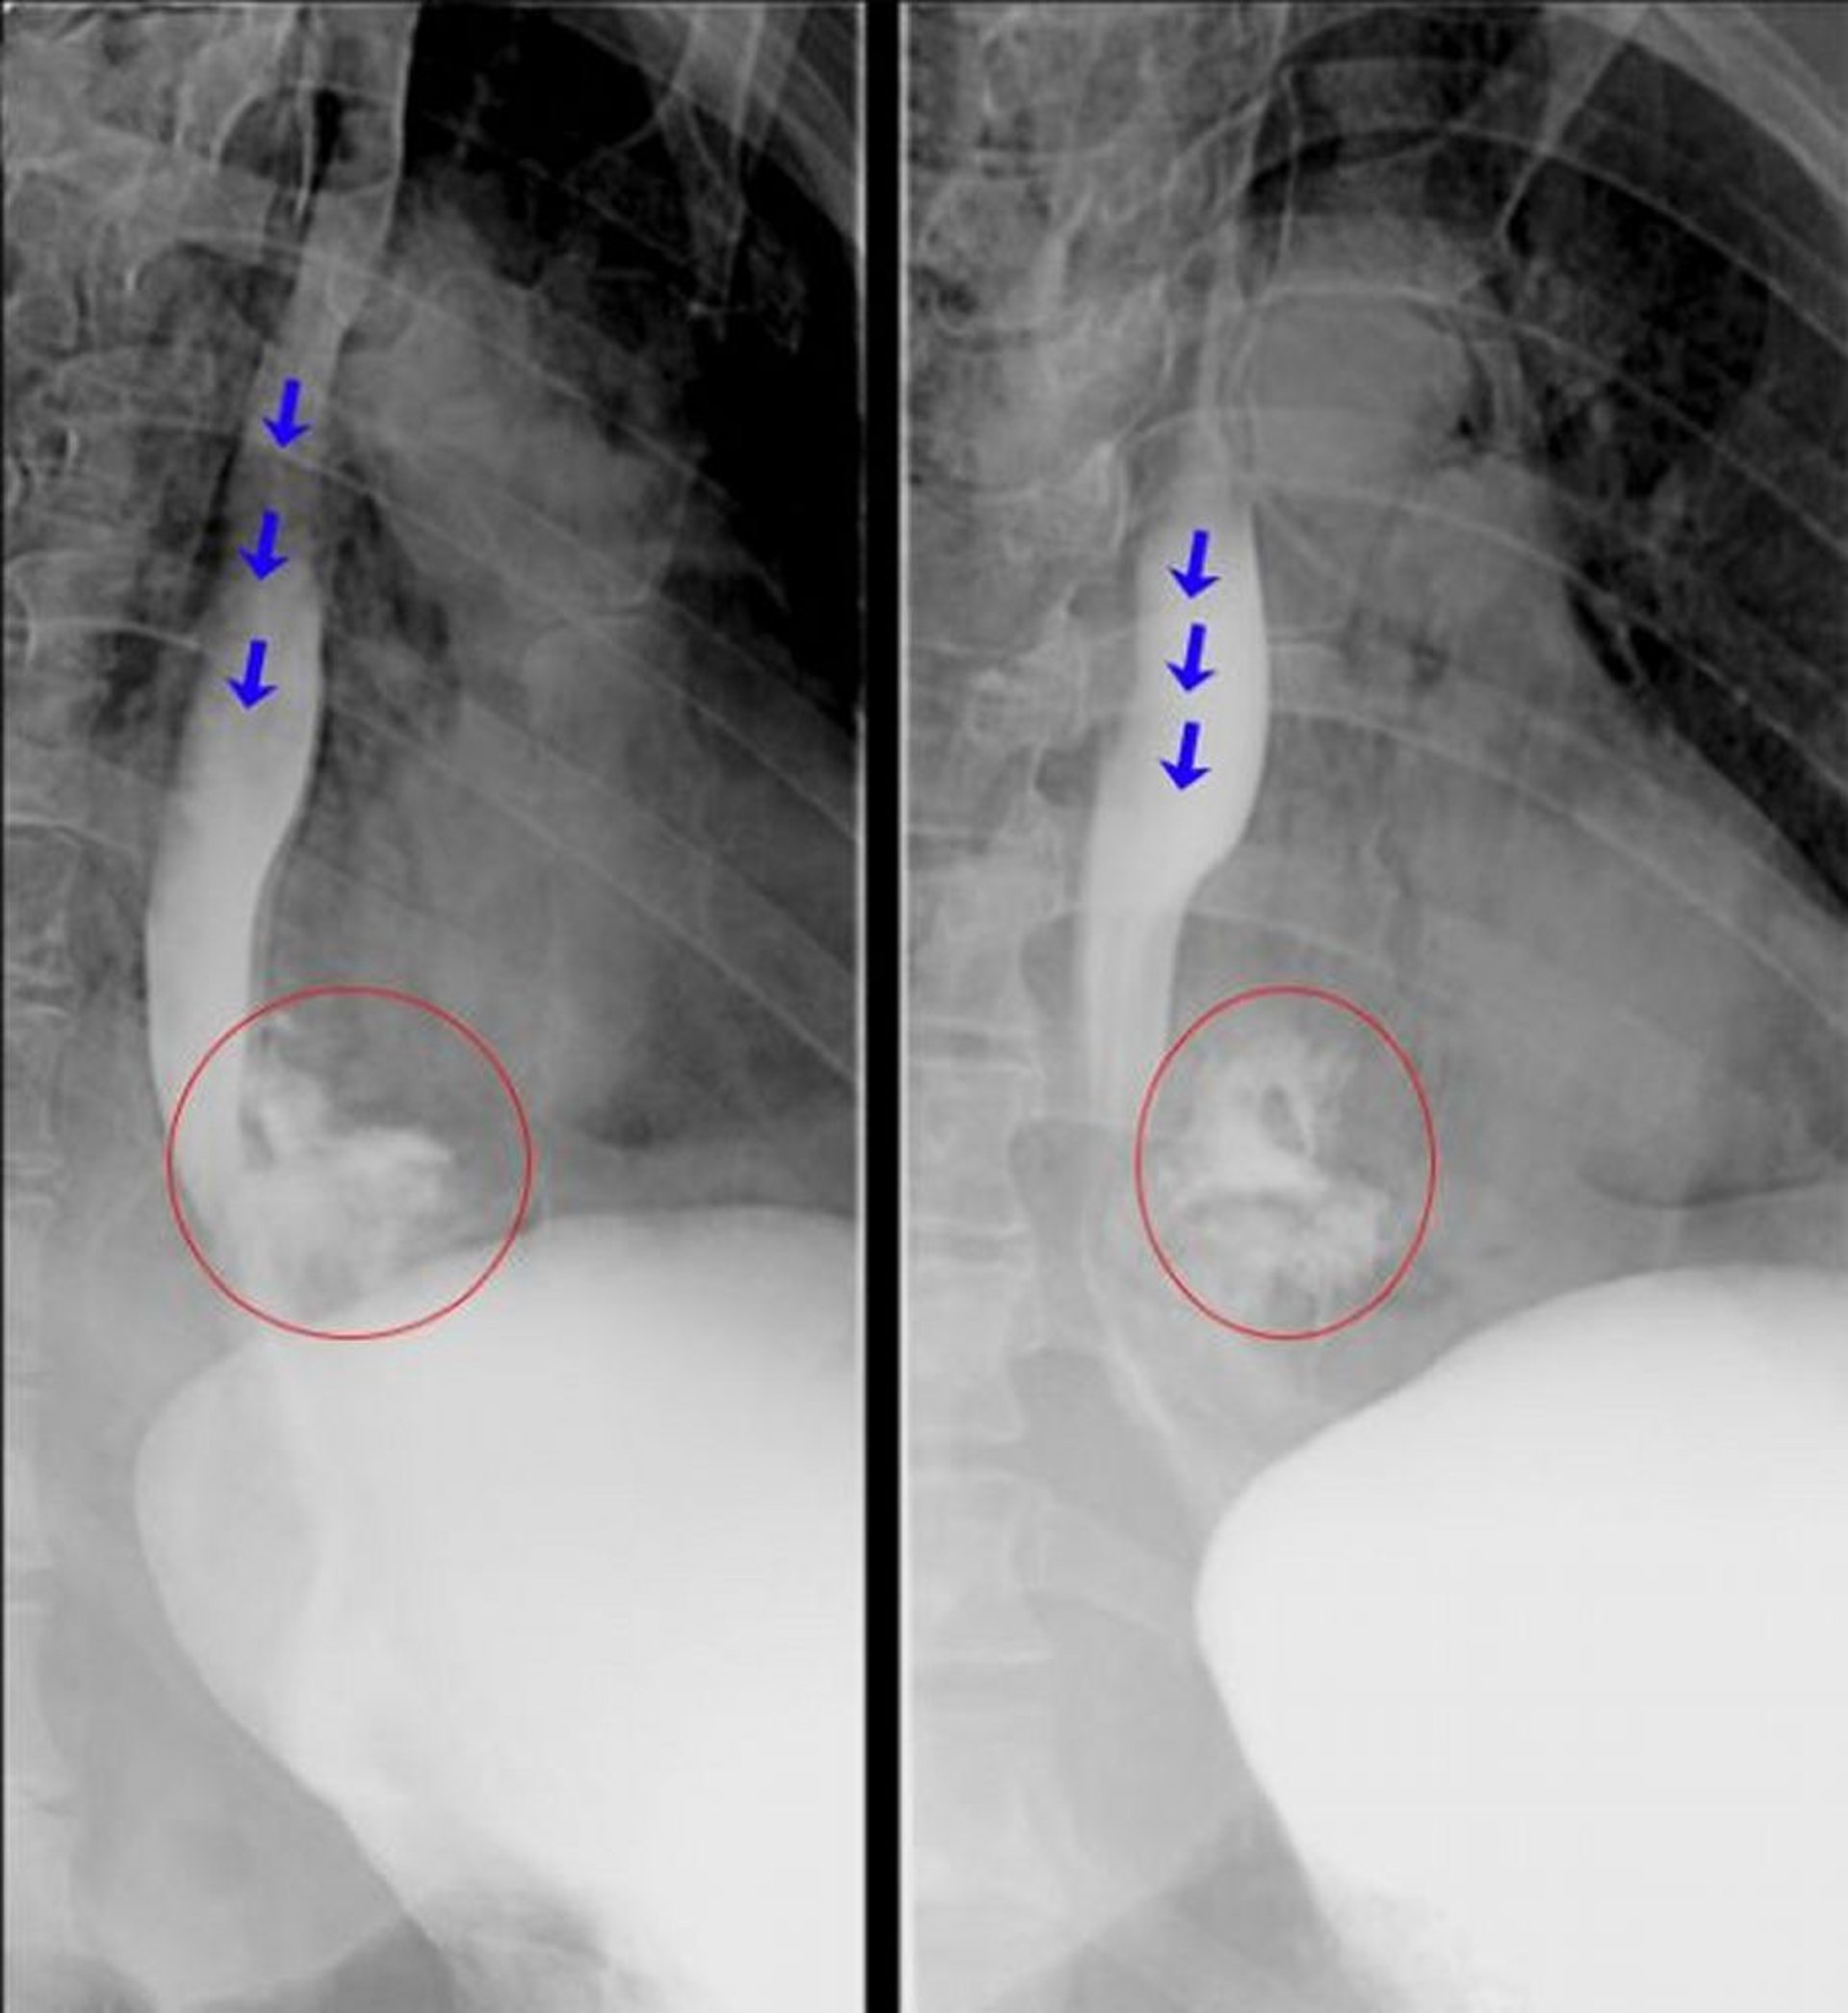

Những hình ảnh chụp thực quản có soi huỳnh quang này cho thấy thuốc cản quang thoát ra rõ ràng từ thực quản đoạn xa phù hợp với thủng thực quản. Mũi tên màu xanh làm nổi bật chất cản quang trong lòng thực quản. Các vòng tròn màu đỏ làm nổi bật chất cản quang đã thoát ra khỏi thực quản.